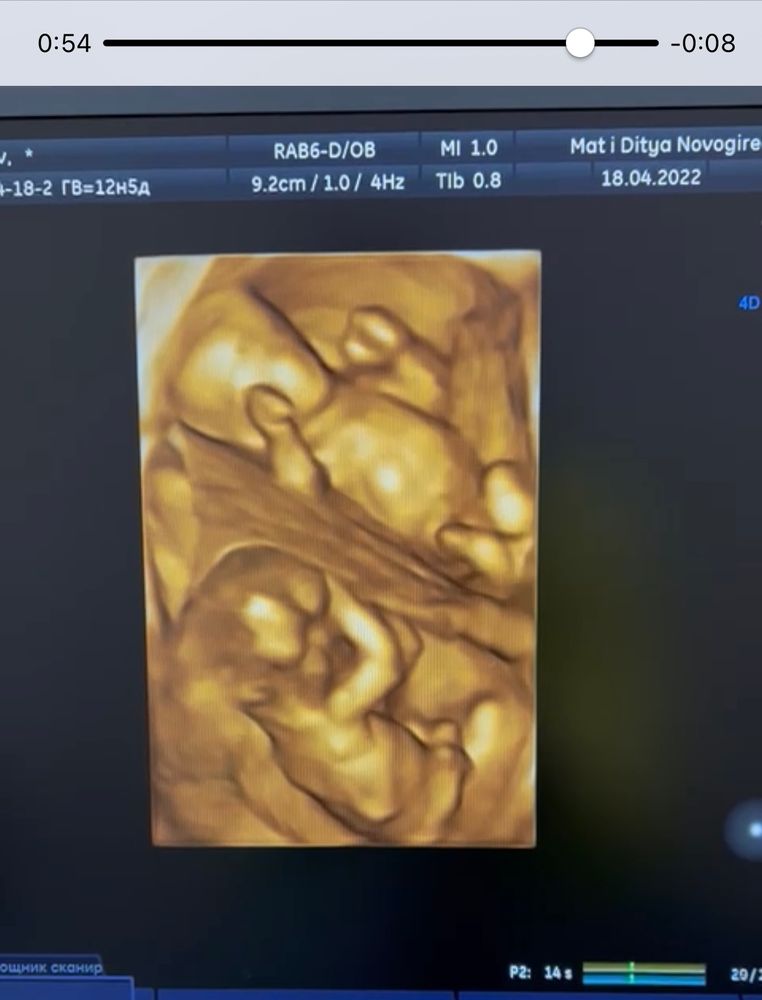

Так вот про УЗИ) Сегодня увидела сразу ДВУХ ЦЕЛЫХ человека)) Это, конечно, просто космос! Один лежал на боку и вроде спал, а второй вовсю толкал своими ножками🥰 По нормам мы по всем проходим. Срок по УЗИ 12-13недель.

Дали заснять видео и даже в 3д показали!)это что-то невероятное!)